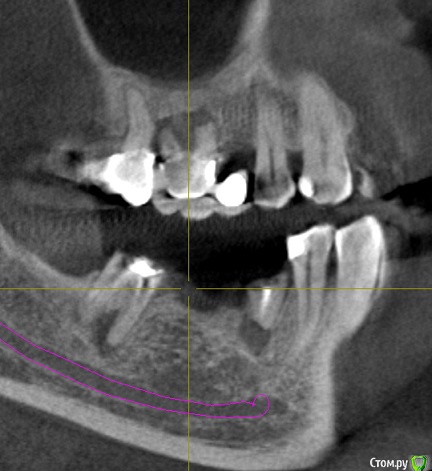

Здравствуйте.  Прошу докторов помочь советом.  Альтернатива  - либо лечить 7-й нижний с кистой (5-й под удаление без вопросов)   и ставить мост на 7-4, либо  оба удалять и ставить импланты.

Внизу пятого тоже киста (10 лет назад делали резекцию корня) или просто область с меньшей плотностью.  Эта область к сожалению выходит в сторону щеки через костную ткань ,  см. 2-й рисунок.

Поэтому или  предложенный вариант с удалением, или лечение 47 и имплантаты в область 46,45.

Спасибо за ответы.   А как Вы считаете, можно  ли в данном случае ставить импланты без наращивания кости ?  На месте 46 нет зуба около 15 лет,    внизу 45-го   киста/темная область    с прямым выходом в сторону  щеки ...